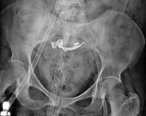

Spontaneous resolution of a spontaneous steinstrasse: a case report

Egemen Tezcan and others

Journal of Surgical Case Reports, Volume 2018, Issue 10, October 2018, rjy252, https://doi.org/10.1093/jscr/rjy252